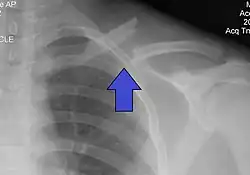

Diagnosis

The basic method to check for a clavicle fracture is by an X-ray of the clavicle to determine the fracture type and extent of injury. In former times, X-rays were taken of both clavicle bones for comparison purposes. Due to the curved shape in a tilted plane X-rays are typically oriented with ~15° upwards facing tilt from the front. In more severe cases, a computerized tomography (CT) or magnetic resonance imaging (MRI) scan is taken. However, the standard method of diagnosis through ultrasound imaging performed in the emergency room may be equally accurate in children.[6]